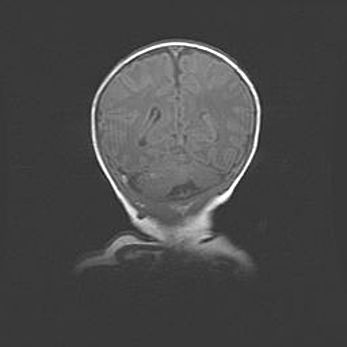

Наружная гидроцефалия с возможной атрофией височных областей.

Возраст: 28 дней

Вес: 3670 г

Пол: мужской

Окружность головы: 38 см

Срок гестации: 40 недель

Гидроцефалия головного мозга у новорожденных – это заболевание, которое характеризуется скоплением избыточного количества спинномозговой жидкости в желудочковой системе головного мозга в результате затруднения её перемещения от места выработки к месту поглощения в кровеносную систему или вследствие нарушения абсорбции. При открытой наружной форме гидроцефалии у новорожденных расширяются и переполняются субарахноидные пространства.

При нормотензивных  формах,  которые,  как  правило,  являются  следствием  перенесенных ишемических  повреждений  паренхимы  мозга,  возможно  сочетание микроцефалии  с нормотензивной гидроцефалией. В основе данных изменений лежит атрофия больших полушарий с преимущественной  локализацией  в  лобно-височных  областях.